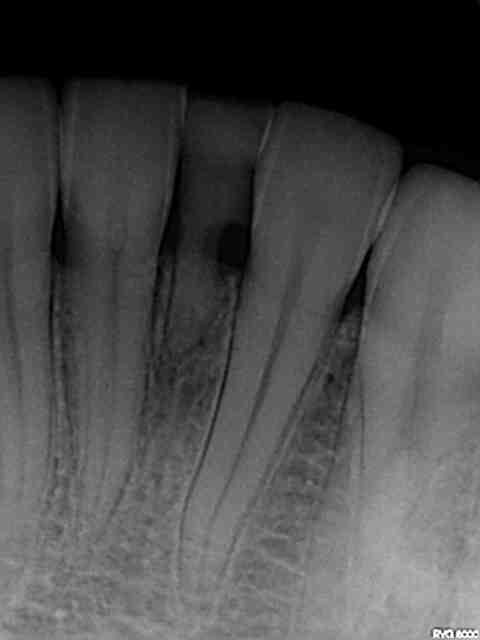

Qu'est ce que vous proposeriez à cette patiente?

71 toujours en place(agénésie ce 31), cariée et très peu de place mésio-distale.

Classe 1 molaire.